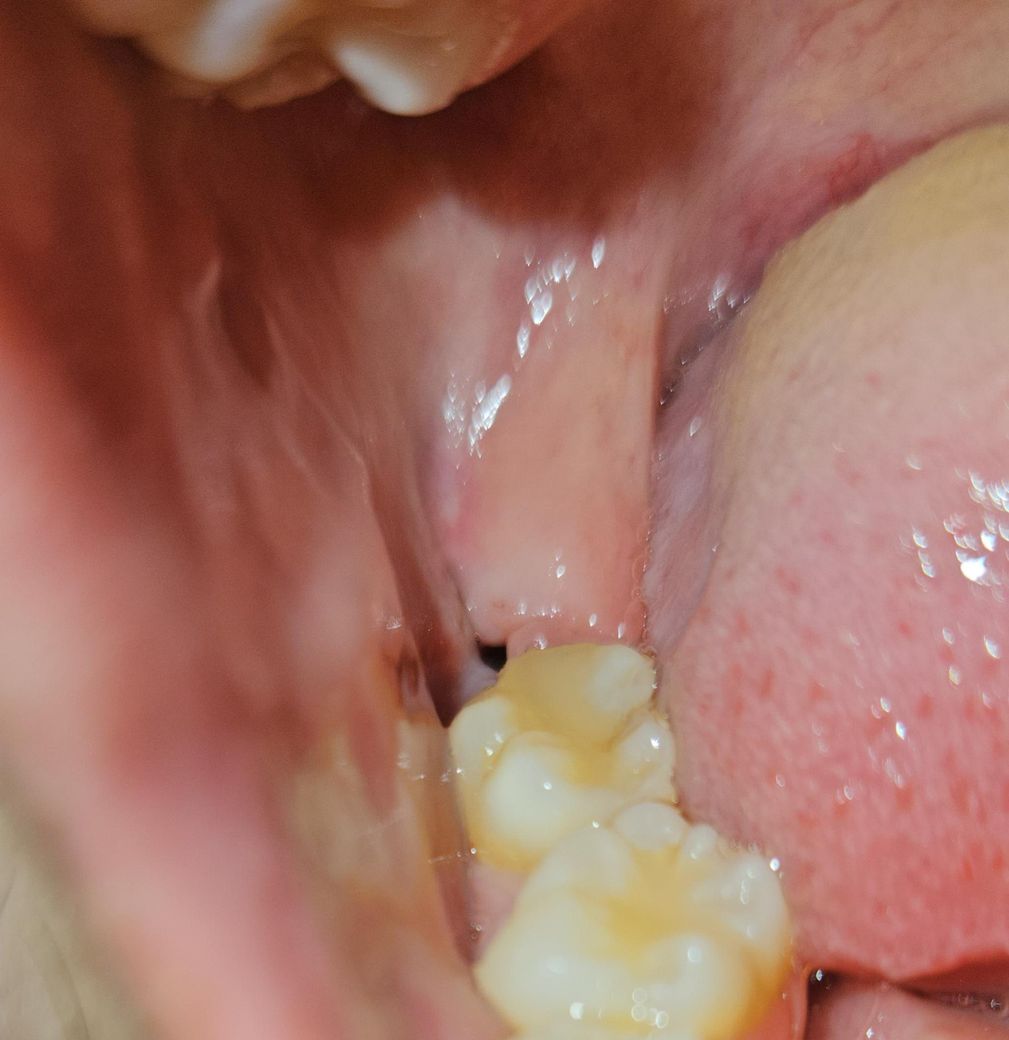

오늘 실밥 제거 했는데 입 벌려보니 무슨 시꺼먼게 보여서 봤는데.. 이게 도저히 구멍이 맞는지... 검정색 실로 꼬맷는데 저는 아무리봐도 실밥 같거든요?... 이게 구멍인가요?.. 너무 까만데... 진짜 뭐 붙어있는거처럼 까만데요... 반대쪽은 매복에 실밥 풀고 구멍이 없었거든요.. 원래 사랑니 뽑고 이렇게 구멍이 뻥 뚫리나요..ㅠㅠㅠㅠㅠ 실밥 제가하는것도 하나도 안아팠고요ㅠㅠ 진짜 몇초만에 끝났어요.. 실밥을 다 제거를 안해주신건가요?.. 과정이 그럴수가 있나요?... 제가 암만 후레시를 비춰봐도 모르겟어요....ㅠㅠㅠ 이거 아물면 어떻게 되는거죠..

• 2번 째 사진

사진에 보이는건 사랑니가 잇던 공간입니다. 시간이 지나면 잇몸이 아물면서 괜찮아 지니 너무 걱정하지마세요.

사진으로 봤을 경우에는 사랑니를 발치한 부위 내부에 구멍이 있는 것으로 보입니다.

사랑니가 크거나 매복되어 있는 사랑의 경우에는 발치한 부위에 구멍이 커 보일 수 있습니다. 이런 부위는 점차 시간이 지나면서 아물게 되면 보통 3개월 정도가 걸리게 됩니다.

실밥 아니고 구멍 맞을 것 같습니다 실밥 풀고도 구멍이 좀 있을 순 있습니다 걱정안하셔도 됩니다